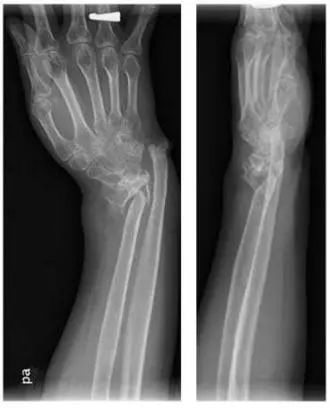

病例一:

诊断:桡骨极远端骨折。

治疗:内固定加外固定治疗。